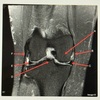

20

Q

Letter D points to the

A

Lateral femoral condyle

21

Letter C points to the

Medial femoral condyle

22

Letter B points to the

Medial

Collateral ligament (MCL)

23

Letter A points to the

24

Letter E points to the

Lateral collateral ligament (LCL)